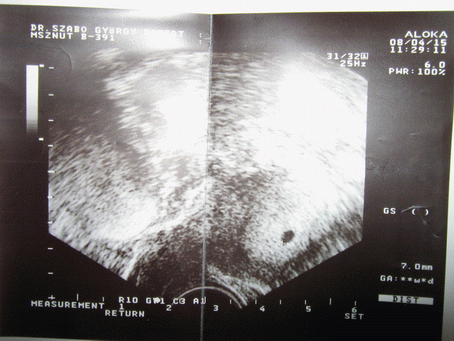

Most 5 hetes, szabályos petezsákot látott a doki, de még benne senkit nem látott ami állítólag normális. Két hét múlva kell visszamenni és akkor már szívhangja is kell hogy legyen. :D

És a sztárfotó, azt mondta a doki hogy kinyomtatja hogy tudjunk rajta veszekedni, hogy kire hasonlít :shock: :lol: :lol: :lol:

Kép

Gyorsan előkerestem az előző terhesség első uh-it. Betöltött 5 hetesen volt a petezsák 9,8 mm és benne egy 2,3 mm embiró. És két hét múlva meg már volt szívhang is. Úgy hogy tényleg lehet ebből még bármmi, hisz még csak most kezdtem az 5. hetet :roll: :D